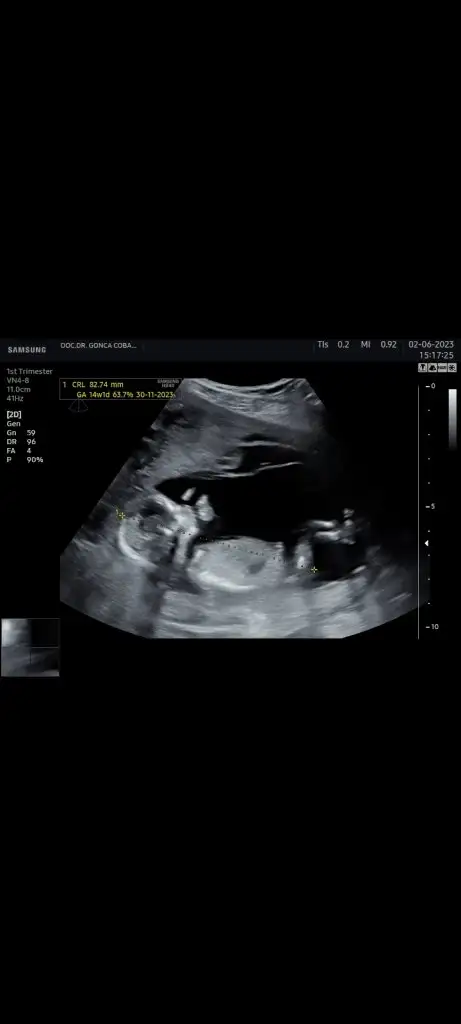

Hepsi karından çekim. Sizden yorum bekliyorum. 1 ay sonra net belli olacak inşallah. 6 haftalık ultrason, 11 haftalık ultrason ve 14 haftalık var. 16 da kendini göstermedi bacakları kapalıydı. Ayrıntılı ultrasonda belli olur artık dedi doktorum. Sizlerin de tahminini bekliyorum.

Eklentiler

• 20230602_222610.webp

20230602_222610.webp

21,8 KB · Görüntüleme: 74

• Screenshot_20230605-223036_Video Player.webp

Screenshot_20230605-223036_Video Player.webp

10,7 KB · Görüntüleme: 72